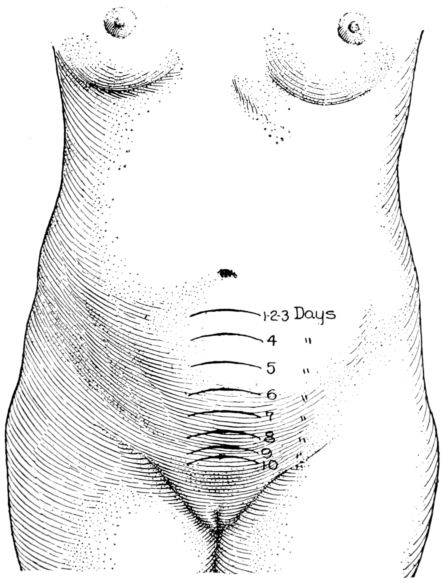

| 116. | Height of fundus on each of first ten days after delivery | 327 |